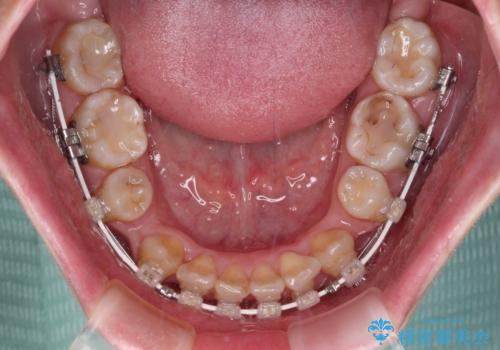

- 矯正装置

- 審美装置

- 2年6ヶ月

- 10-30回

デコボコが強いため小臼歯4本を抜歯し、上顎正中を左側に移動させるために補助装置を使用して、ワイヤー装置にて矯正治療を行うこととしました。